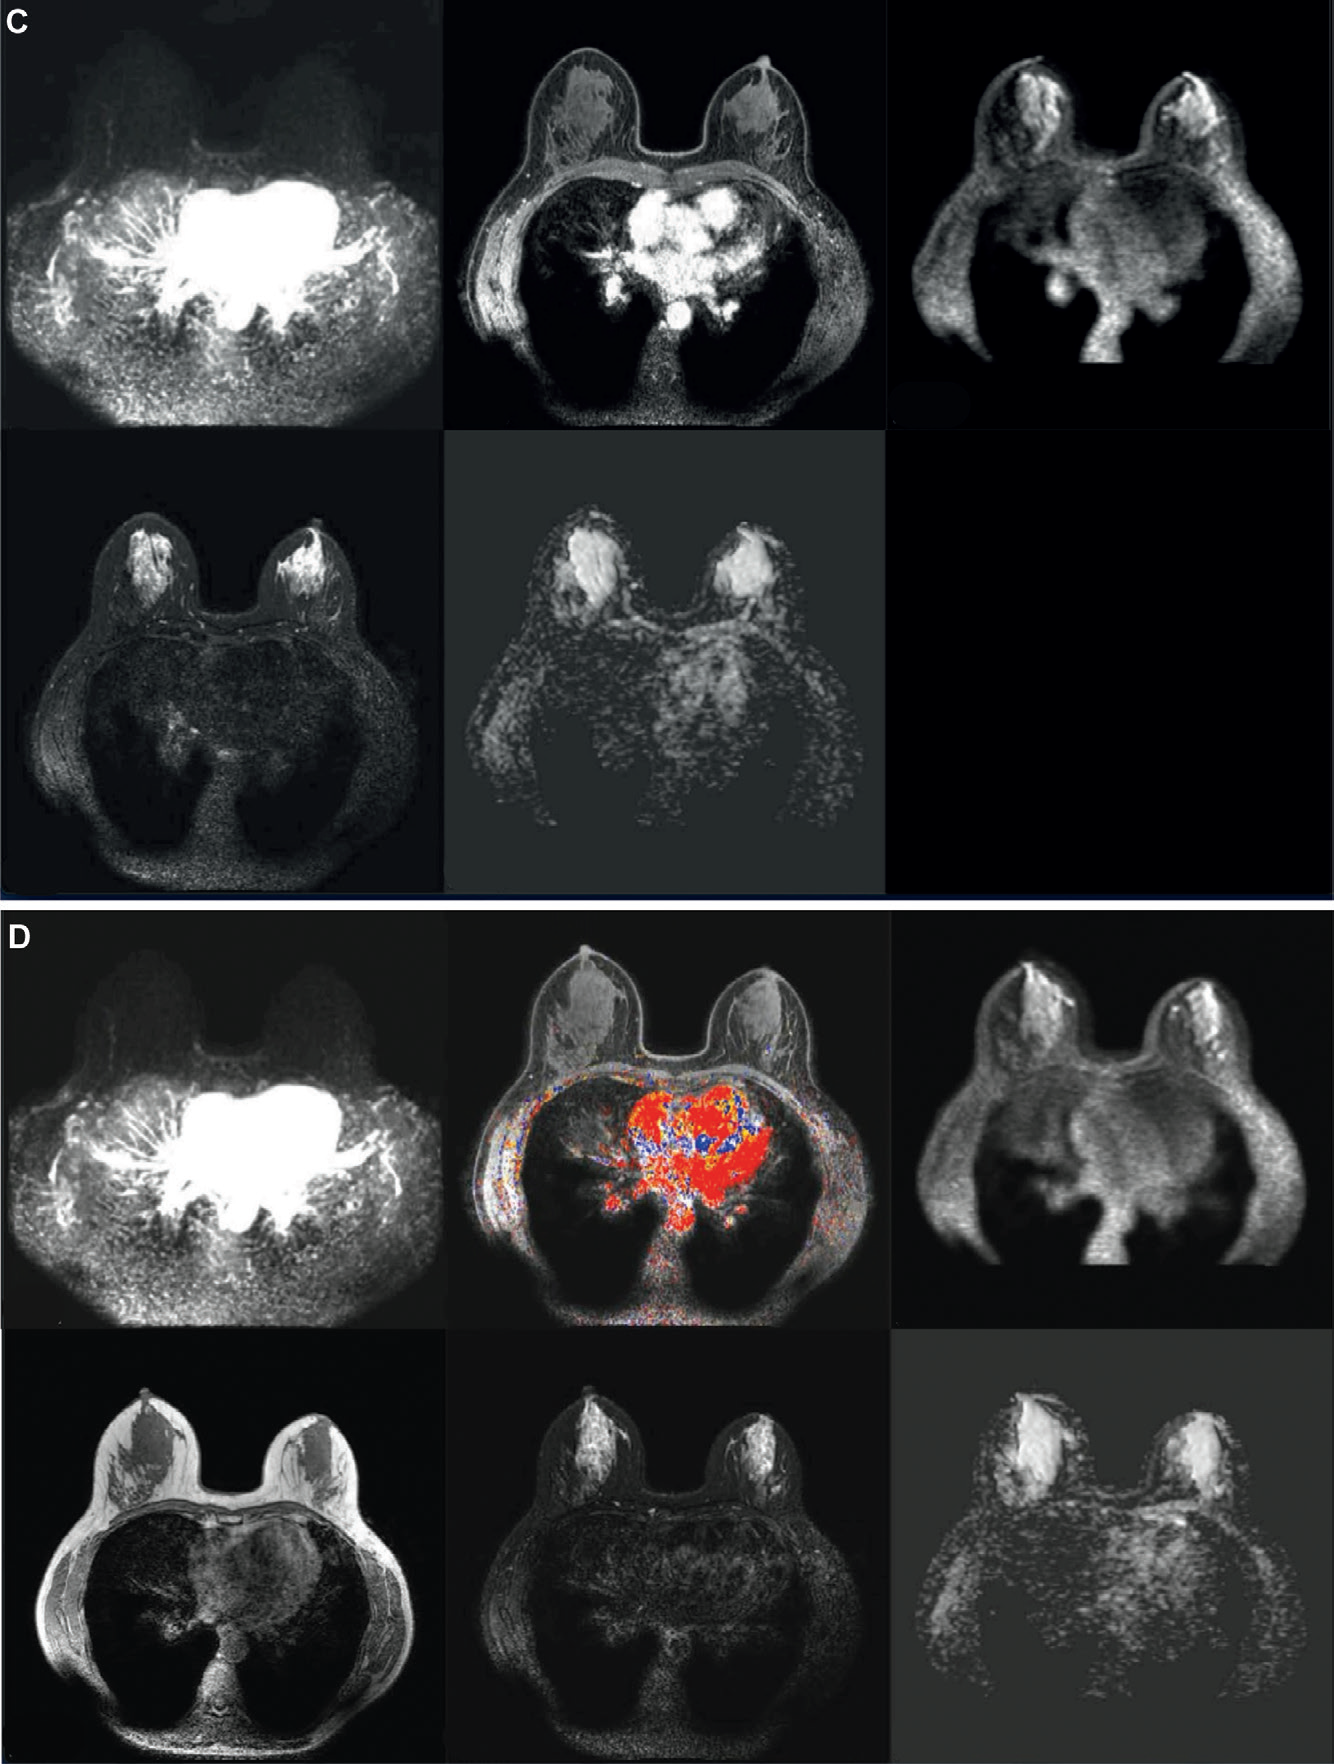

3. 临床价值:典型病例的极简协议表现

-

真阳性案例:6mm 不规则肿块,Step 1 显示早期快速强化(BI-RADS 4 类),活检证实浸润性癌。全参数序列(T2 低信号、DWI 受限、Type III 曲线)仅验证恶性,未改变召回决策。

-

假阳性案例:7mm 肿块 Step 1 误判为 BI-RADS 4 类,全参数序列同样支持恶性特征,但活检为硬化性腺病。提示极简协议的假阳性率与全参数相当。